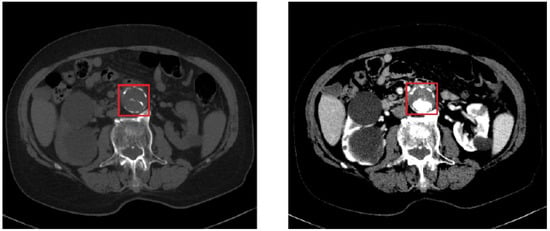

In Figure 3, we can see the comparison between a basal CT image (i.e., without contrast medium) and a CT image with contrast medium (in the arterial phase) depicting an AAA. The difference is evident: the image on the left gives us an idea only of the size of the dilation, while the image on the right shows how much the vessel is occluded.

Figure 3. On the left, basal CT image in the presence of an AAA. In the red square (the so called region of interest, ROI) is depicted the aorta artery. On the right, CT image with contrast medium, corresponding to the same CT section shown on the left.